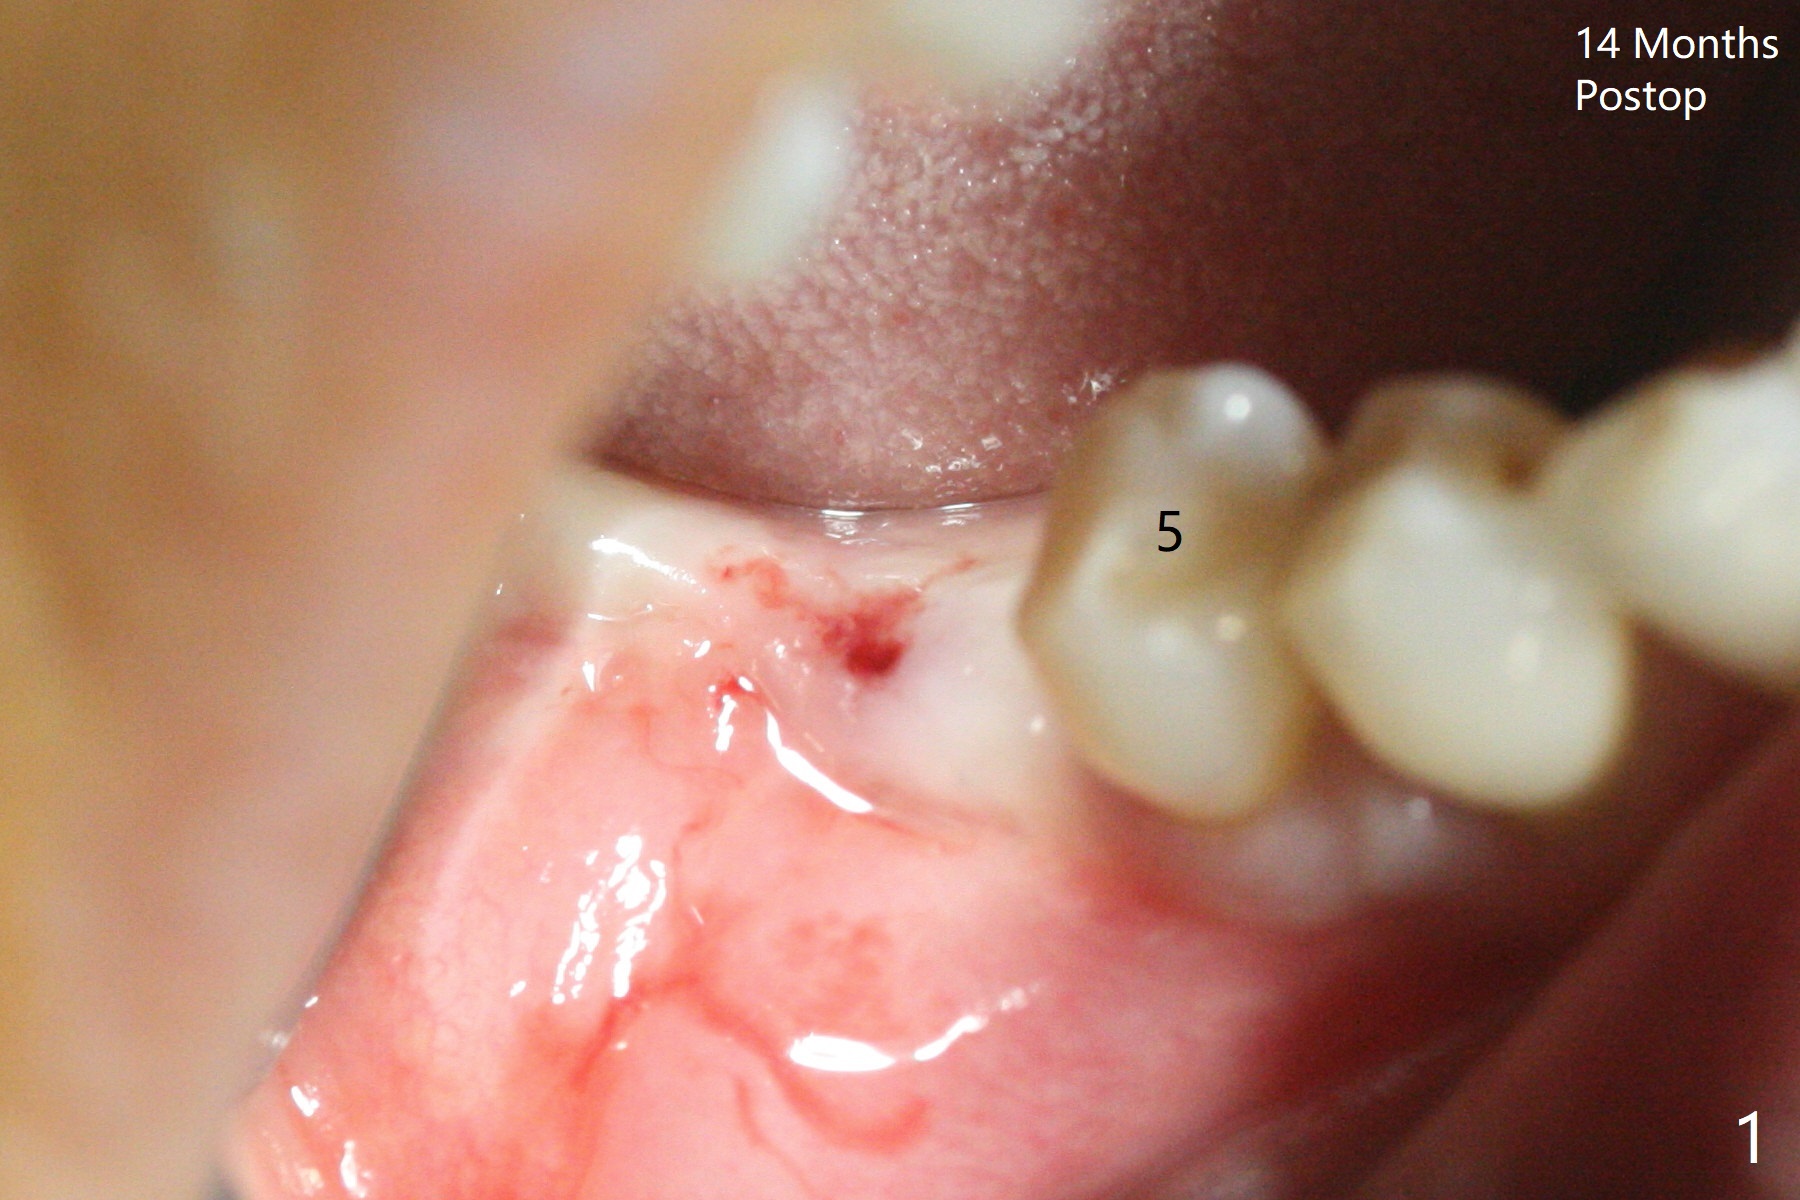

74岁女,右下6因植牙周围炎,植体取出,植骨,术后14个月回来做导板植牙术,局部infiltration时,发现位点中央有些分泌物,刮匙证实有一个瘘道(图一),翻瓣似乎不可避免,骨质缺损没有完全愈合(图二),其实仔细温习术前CT也能发现缺损(图三),导板钻洞位于缺损近中(图四:白圆圈),随着钻头直径增大,钻洞会偏移远中(图四:箭头)和颊侧(由于舌侧骨板厚,颊侧骨板低)。因此用过4毫米钻头后,植入4毫米报废IS植体,接近颊侧。同时为了防止植体断裂,选择五级钛植体(图五)。由于扭力低(手植入,有间隙:图五:<),包埋,使用自体骨和异体骨(皮质,*)。覆盖Osteogen tape后,PGA缝合,牙周胶水(图六)。如果植入4.5毫米植体,后者会更偏移远中。